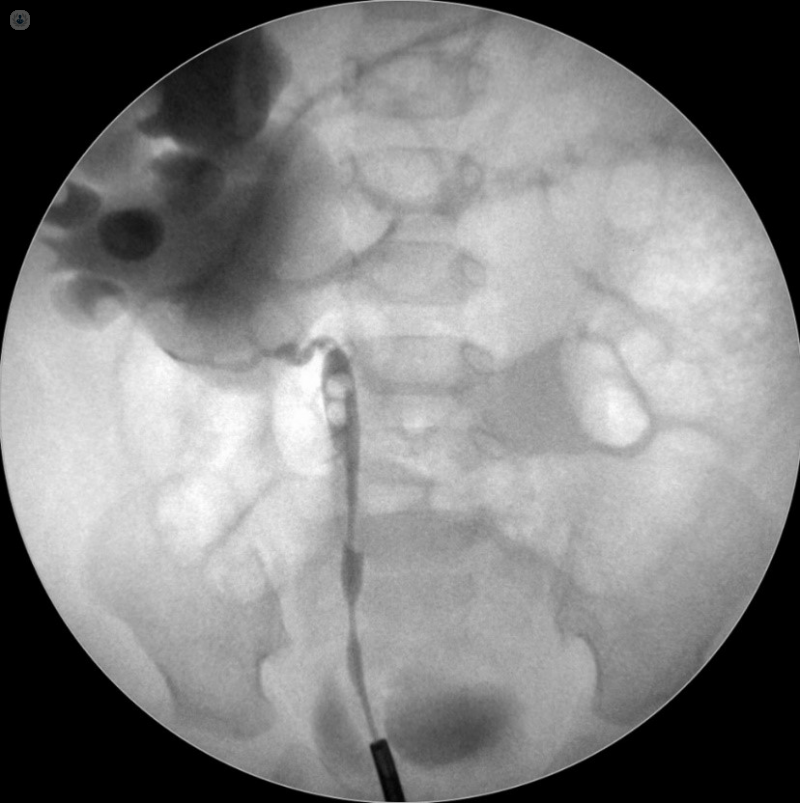

Hydronephrosis

Hydronephrosis is swelling of the kidney due to a build-up of urine, usually caused by a blockage. We identify the cause through imaging and manage it with procedures to relieve the obstruction and preserve kidney function.

PUJ Obstruction

Pelvi-ureteric junction (PUJ) obstruction is a narrowing where the kidney meets the ureter, leading to poor drainage and swelling. It can be corrected with minimally invasive or robotic surgery to restore normal urine flow and protect kidney health. The robotic system is only available in the NHS at present.